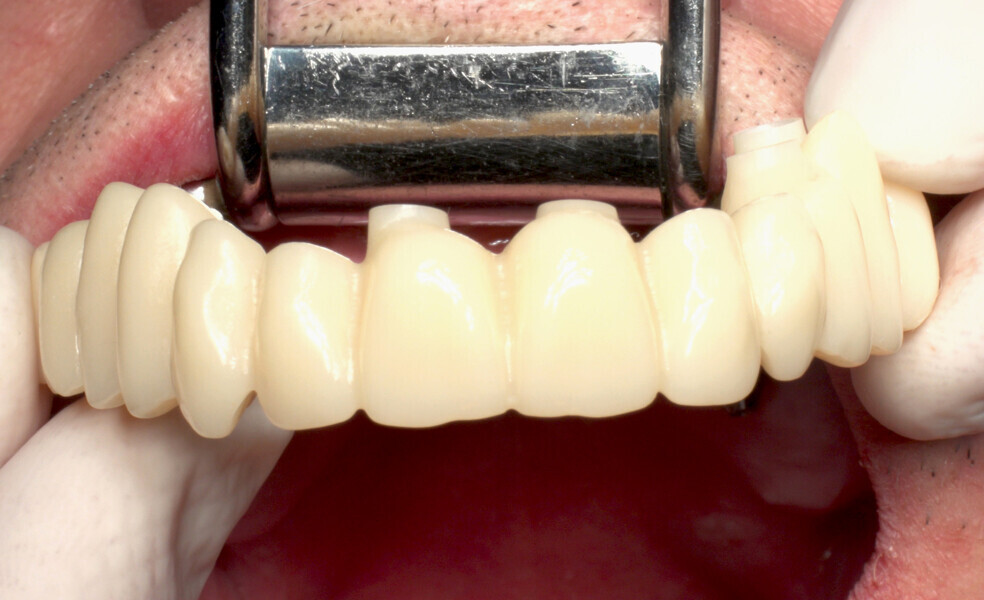

The fully digital Pro Arch protocol